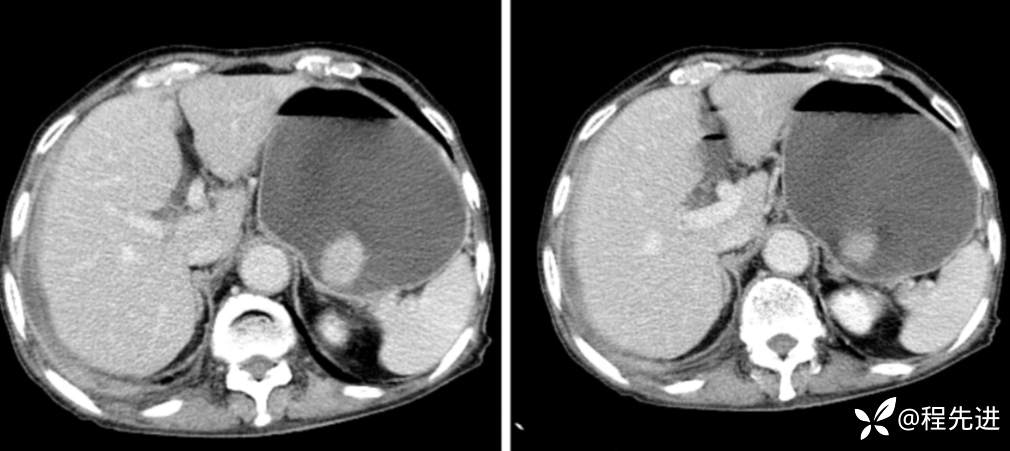

CT

平扫

动脉期

门脉期

延迟期